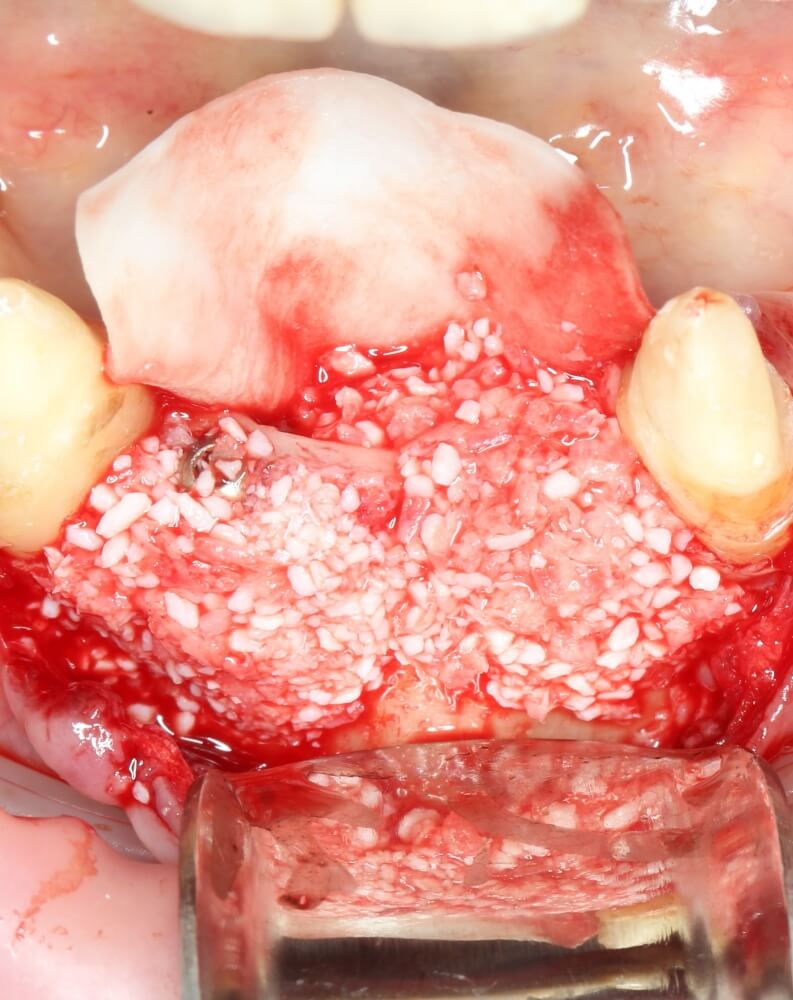

Рекомендации по установке имплантов. Для всех. Часть V.